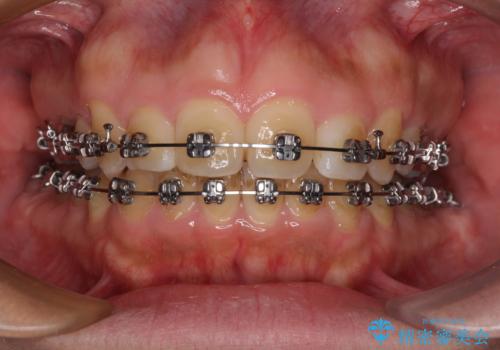

マウスピース矯正でもワイヤー矯正でも対応可能でしたが、患者様の希望によりワイヤー装置による矯正治療を行うこととしました。

ワイヤー矯正ということで、上顎大臼歯を後方に移動するための補助装置を併用して、積極的に前歯を引っ込めていくこととしました。